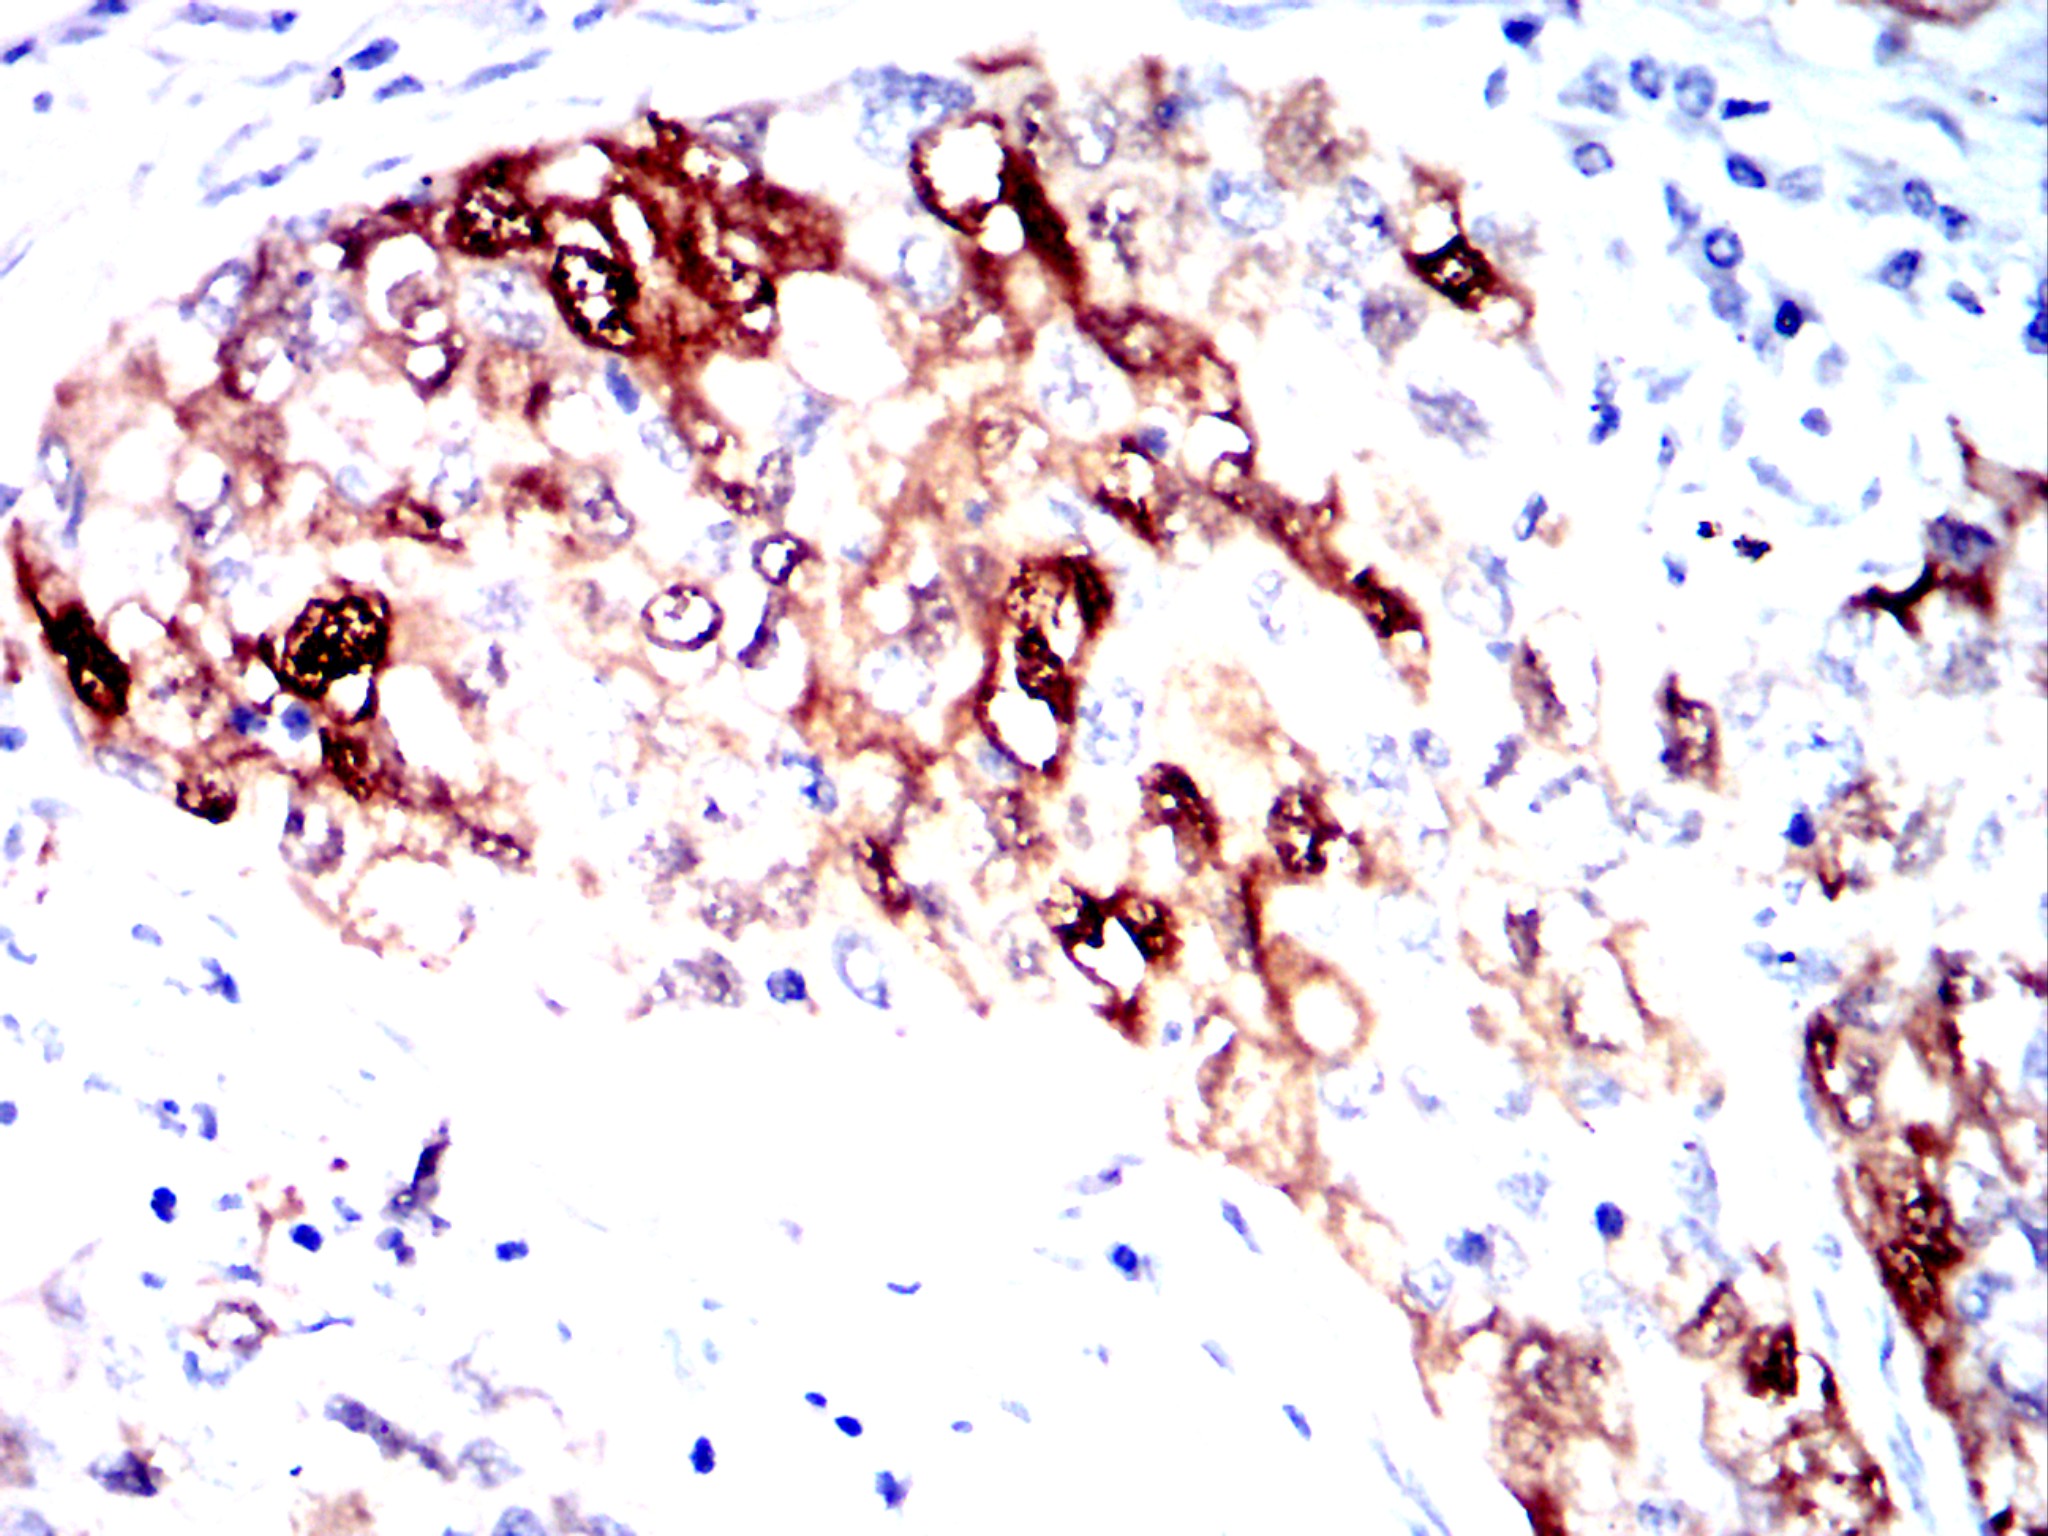

分类: 科研抗体货号: 32454别名: CEA;CD66e应用: IHC反应种属: Human